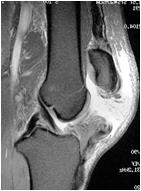

В таком случае более объективным является рентгенологическое исследование. Основным признаком разрыва удерживающих связок надколенника служило увеличение диастаза между отломками по задней поверхности при сгибании голени или даже при сокращении четырехглавой мышцы (рис. 55).

Рис. 55. Рентген-снимки и МРТ отрывных переломов и разрыва собственной связки надколенника.

Таким образом, сопоставление всех полученных данных о состоянии разгибательного аппарата коленного сустава даже в первые дни после возникновения травмы, что помогает в решении вопроса необходимости хирургического вмешательства в ранние сроки.